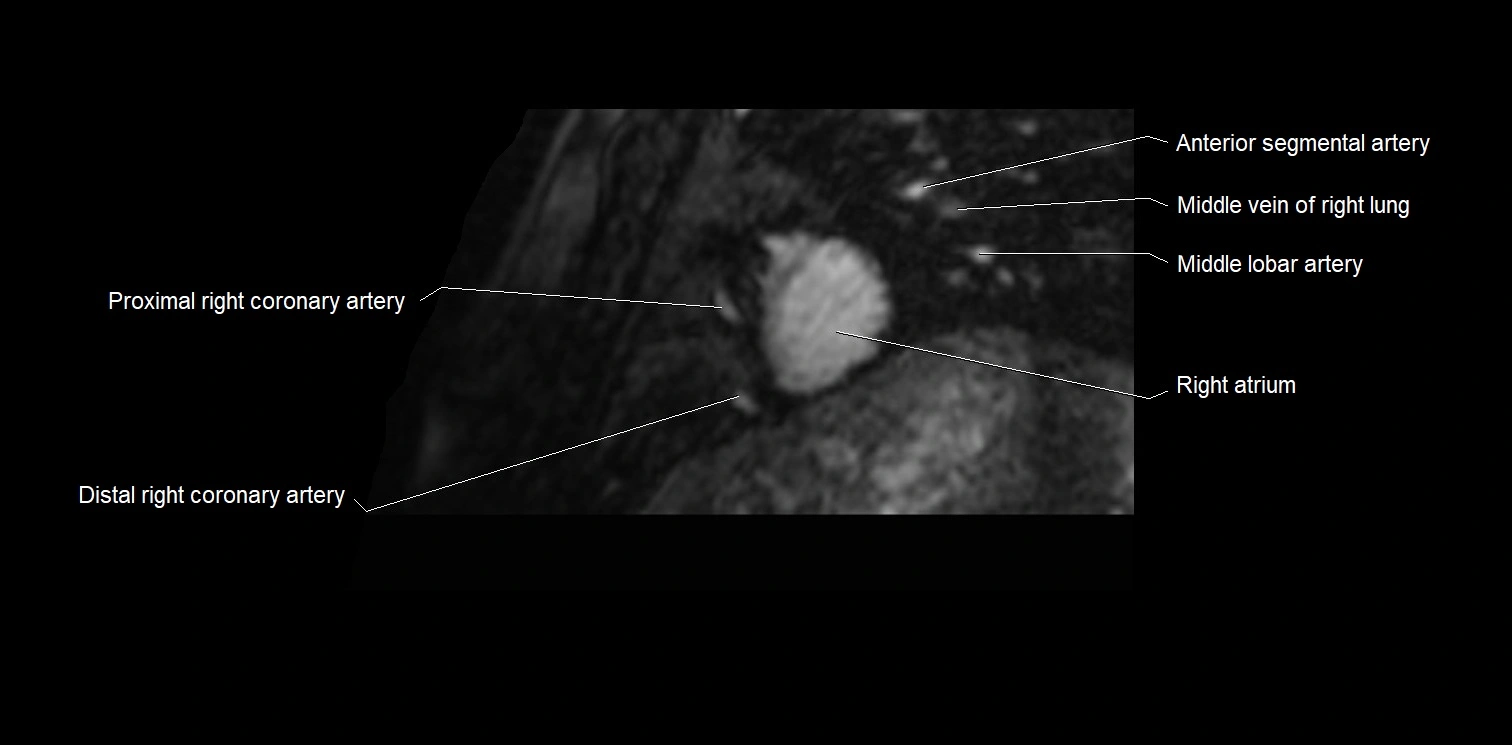

MRI image